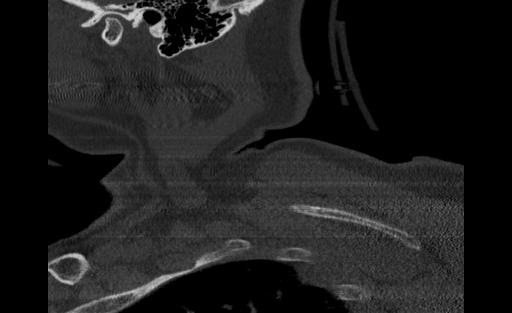

Below are examples of three different patients. The first image is the axial view from the center of the spine. The second image is the center most slice of our converted sagittal view:

Patient 1 Axial Scan Slice

Patient 1 Sagittal Scan Slice

Figure 2. Patient 1 Axial and Sagittal Scans

From the examples above, we see that the axial scans that have uniform size and shape, is transformed into a sagittal view using consecutive axial scans. One unintended consequence of this transformation is that we have a variable size sagittal image where the axial images where all uniform square size. Many models need a uniform size input to be able to correctly predict the classification labels and this was a major roadblock that we ran into when running the HuggingFace models on our CT scan dataset.